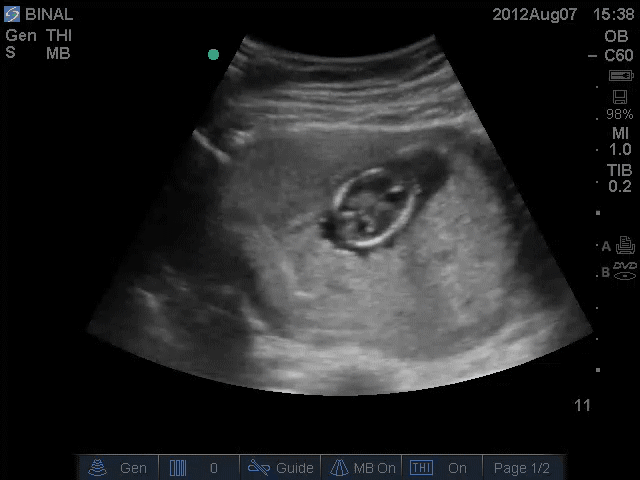

Prenatal Diagnostic Procedures

Following PRENATAL DIAGNOSTIC PROCEDURES are performed at shobha diagnostic centre:

Systematic fetal sonography is the first step in detecting and diagnosing the birth defects, however to diagnose chromosomal abnormalities and certain hereditary syndromes more advanced tests are needed.